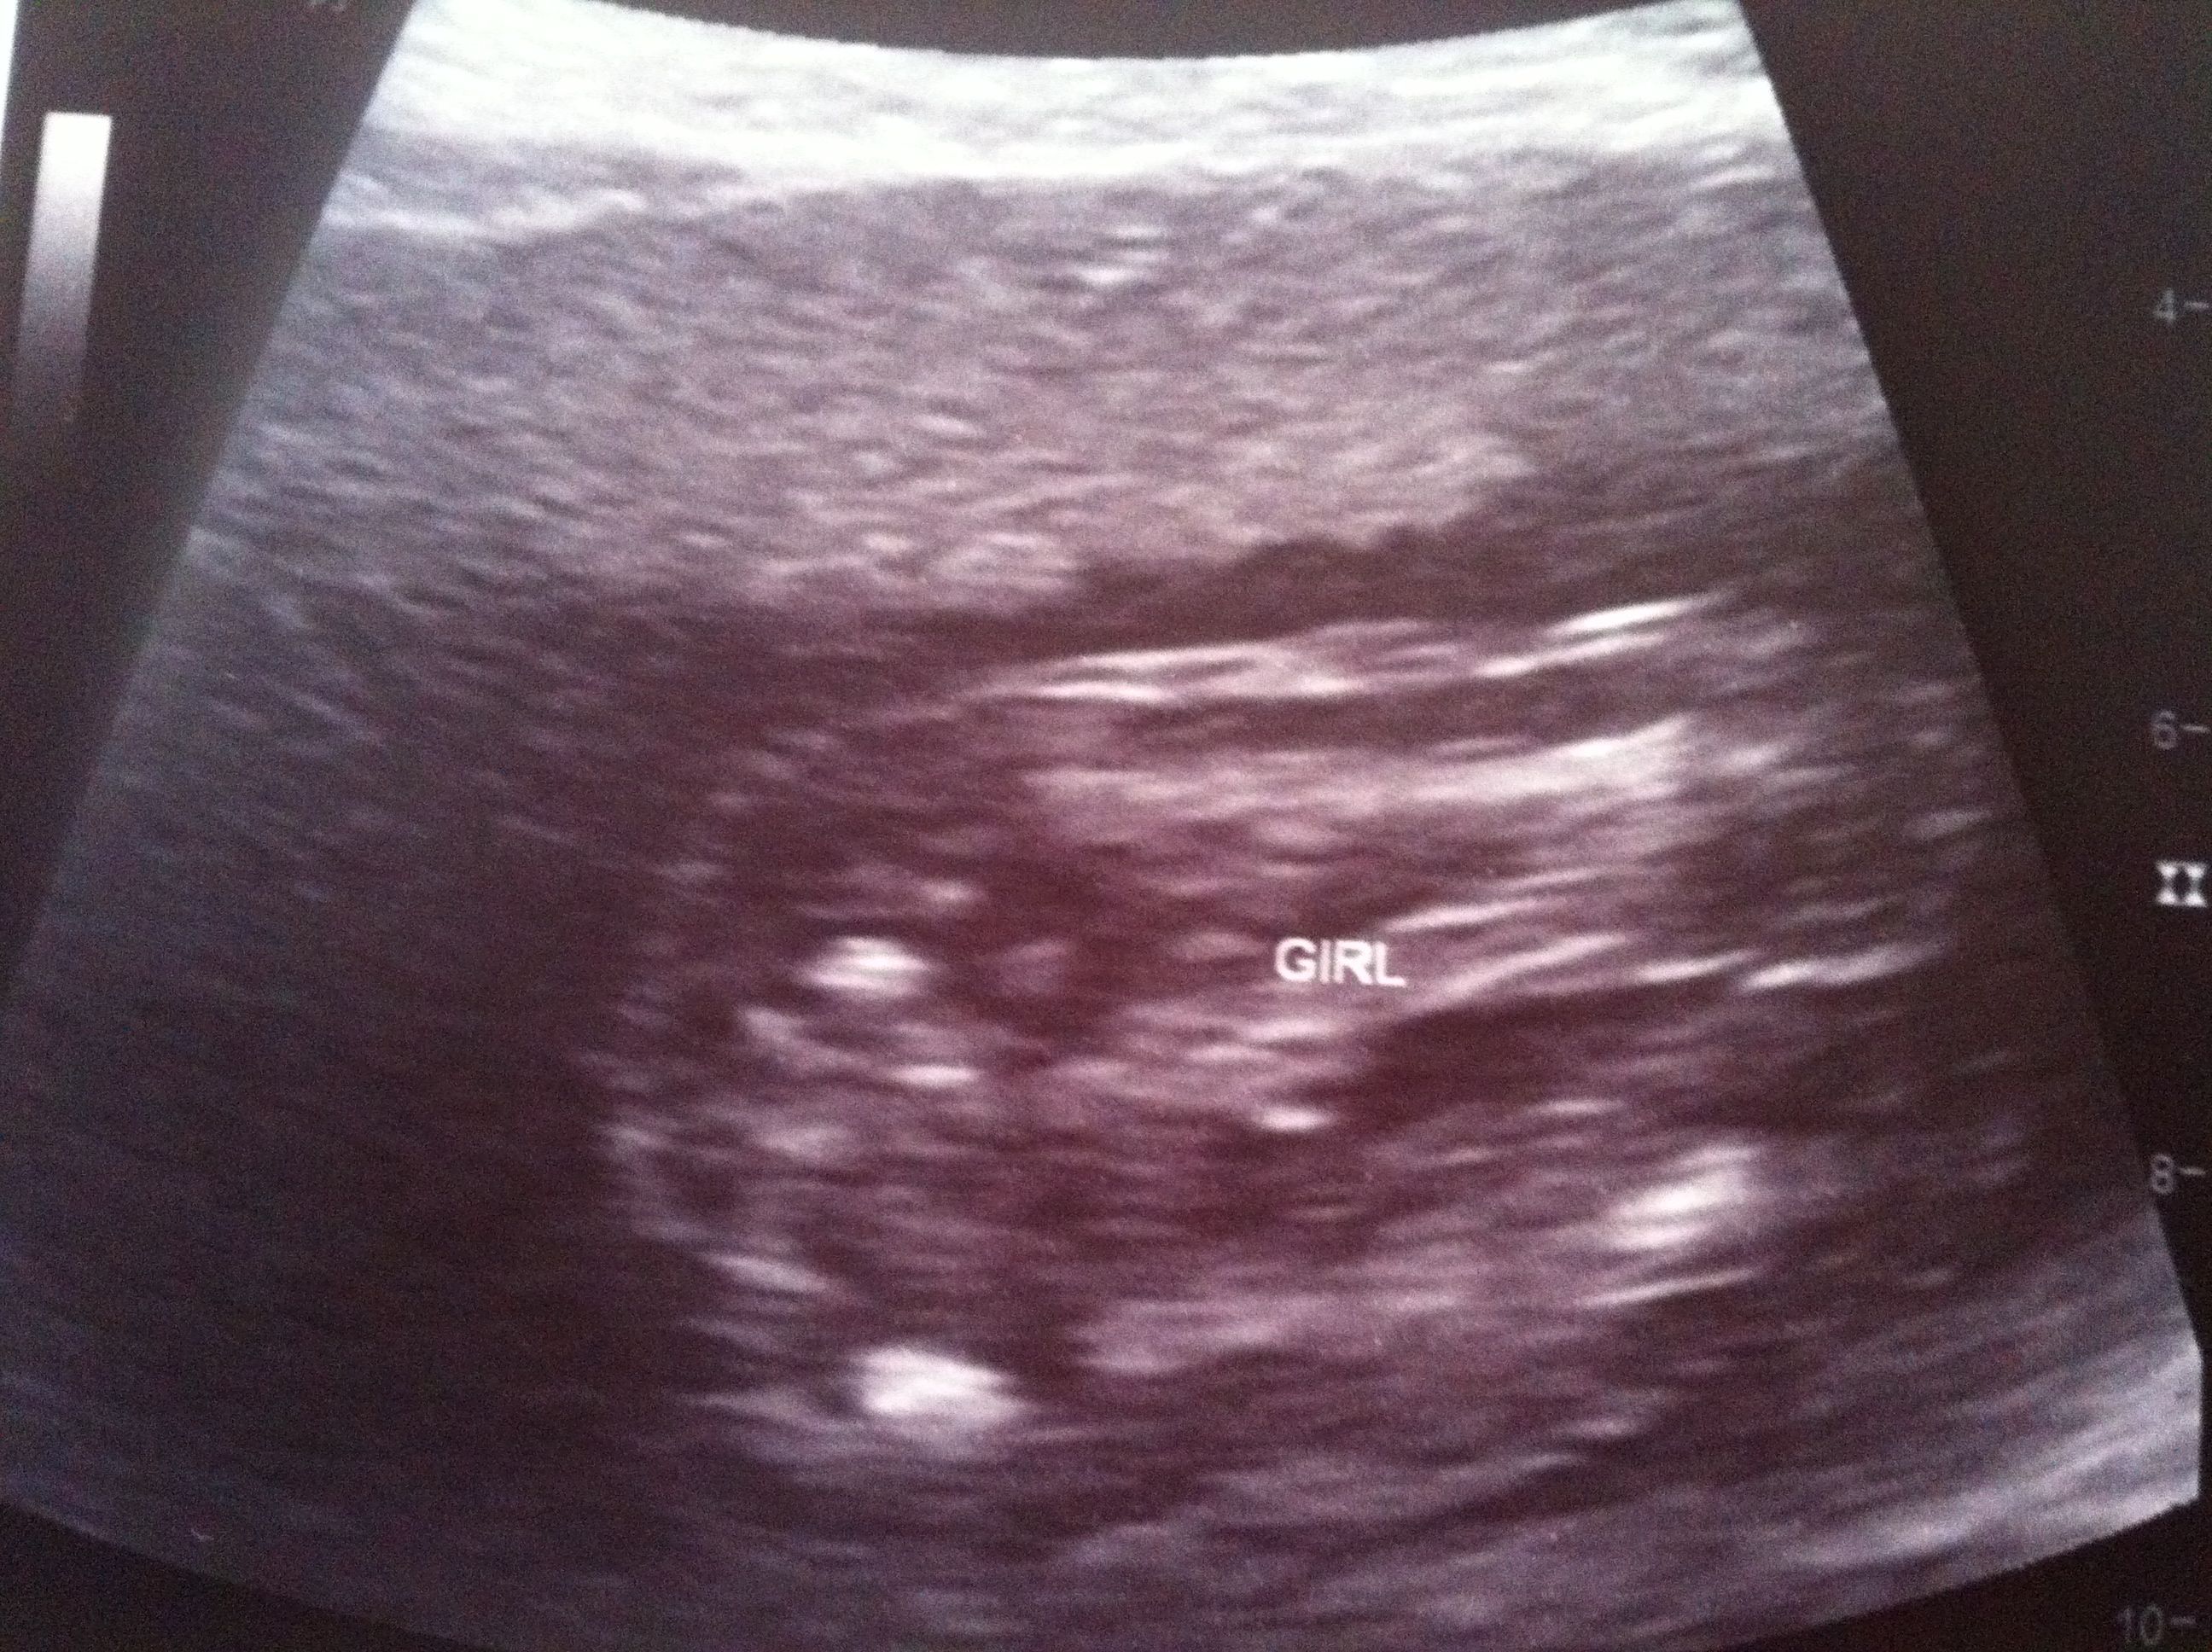

14 week u/s pointed to boy, 20 week u/s leaning towards girl. . . .need another opinion here. :-)

I had a funsies ultrasound in Illinois and was led to believe that my little one was a boy, which fell in line with my thoughts and feelings. However, I had the anatomy scan at 20 weeks and the tech said that she was "pretty sure" then "99.9" sure that it was a little girl.

Although I know that she is good at her job, I just am not feeling it. Yes, I want a 10 finger and 10 toed baby with all body parts in the correct places, but I am just not 100% in agreement with her.